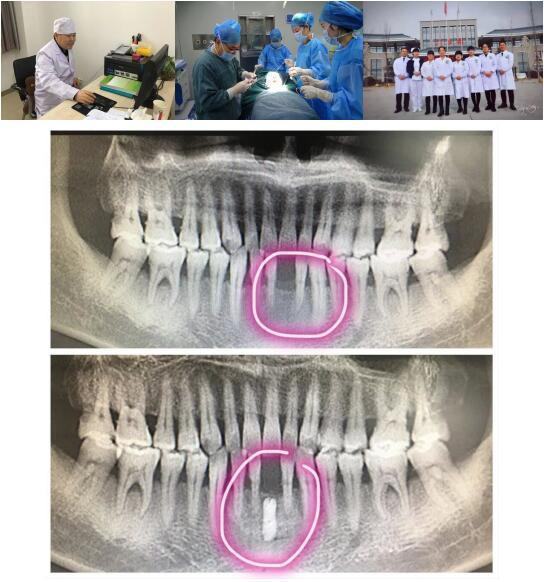

21点游戏攻略站 高陵院区口腔科成功开展一例GBR引导骨再生技术种植牙